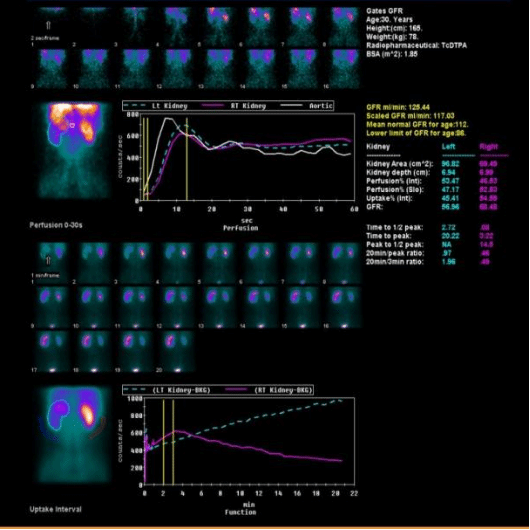

3、肾积水患者评估患肾功能

左图,男,30岁,左肾积水,左肾功能大致正常,左上尿路梗阻。

右图,女,52岁,右肾积水,致右肾显示不清、几乎无功能。

以上三组病例告诉我们,相同的疾病,对肾脏的影响可能不同,肾动态显像可以帮助我们定量的判断两个肾脏分别的功能。